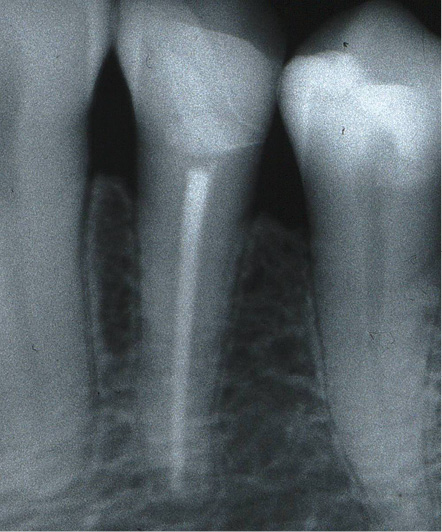

Fig. 3c Final control of endodontic treatment.

Fig. 3d X-ray control after 18 years.